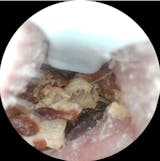

Ich habe eine starke Ohrenschmalzproduktion und es entstehen regelmäßig Propfen, die in der Vergangenheit regelmäßig vom Ohrenarzt entfernt werden mussten.

Mit diesel Gerät kann ich selbst in regelmäßigen Abständen das Ohr vom gröbsten Ohrenschmalz befreien. Mit diesem Gerät tut es überhaupt nicht weh, die Aufnahmen der Kamera sind sehr gut. Mit etwas Geduld, Übung und Vorsicht kann man das Ohr wirklich sehr gut reinigen, ohne es zu verletzen. Ich kann das Produkt ohne Vorbehalte weiterempfehlen und würde es wieder kaufen.

Meine Ohren waren ziemlich dreckig, hab damit aber fast alles rausbekommen. Bin zufrieden

Meine Ohren waren soooo verstopft, das hätte ich mir nie gedacht. Hab aber zum Glück alles rausbekommen, das Gefühl ist auch richtig angenehm gewesen, fast schon satisfying